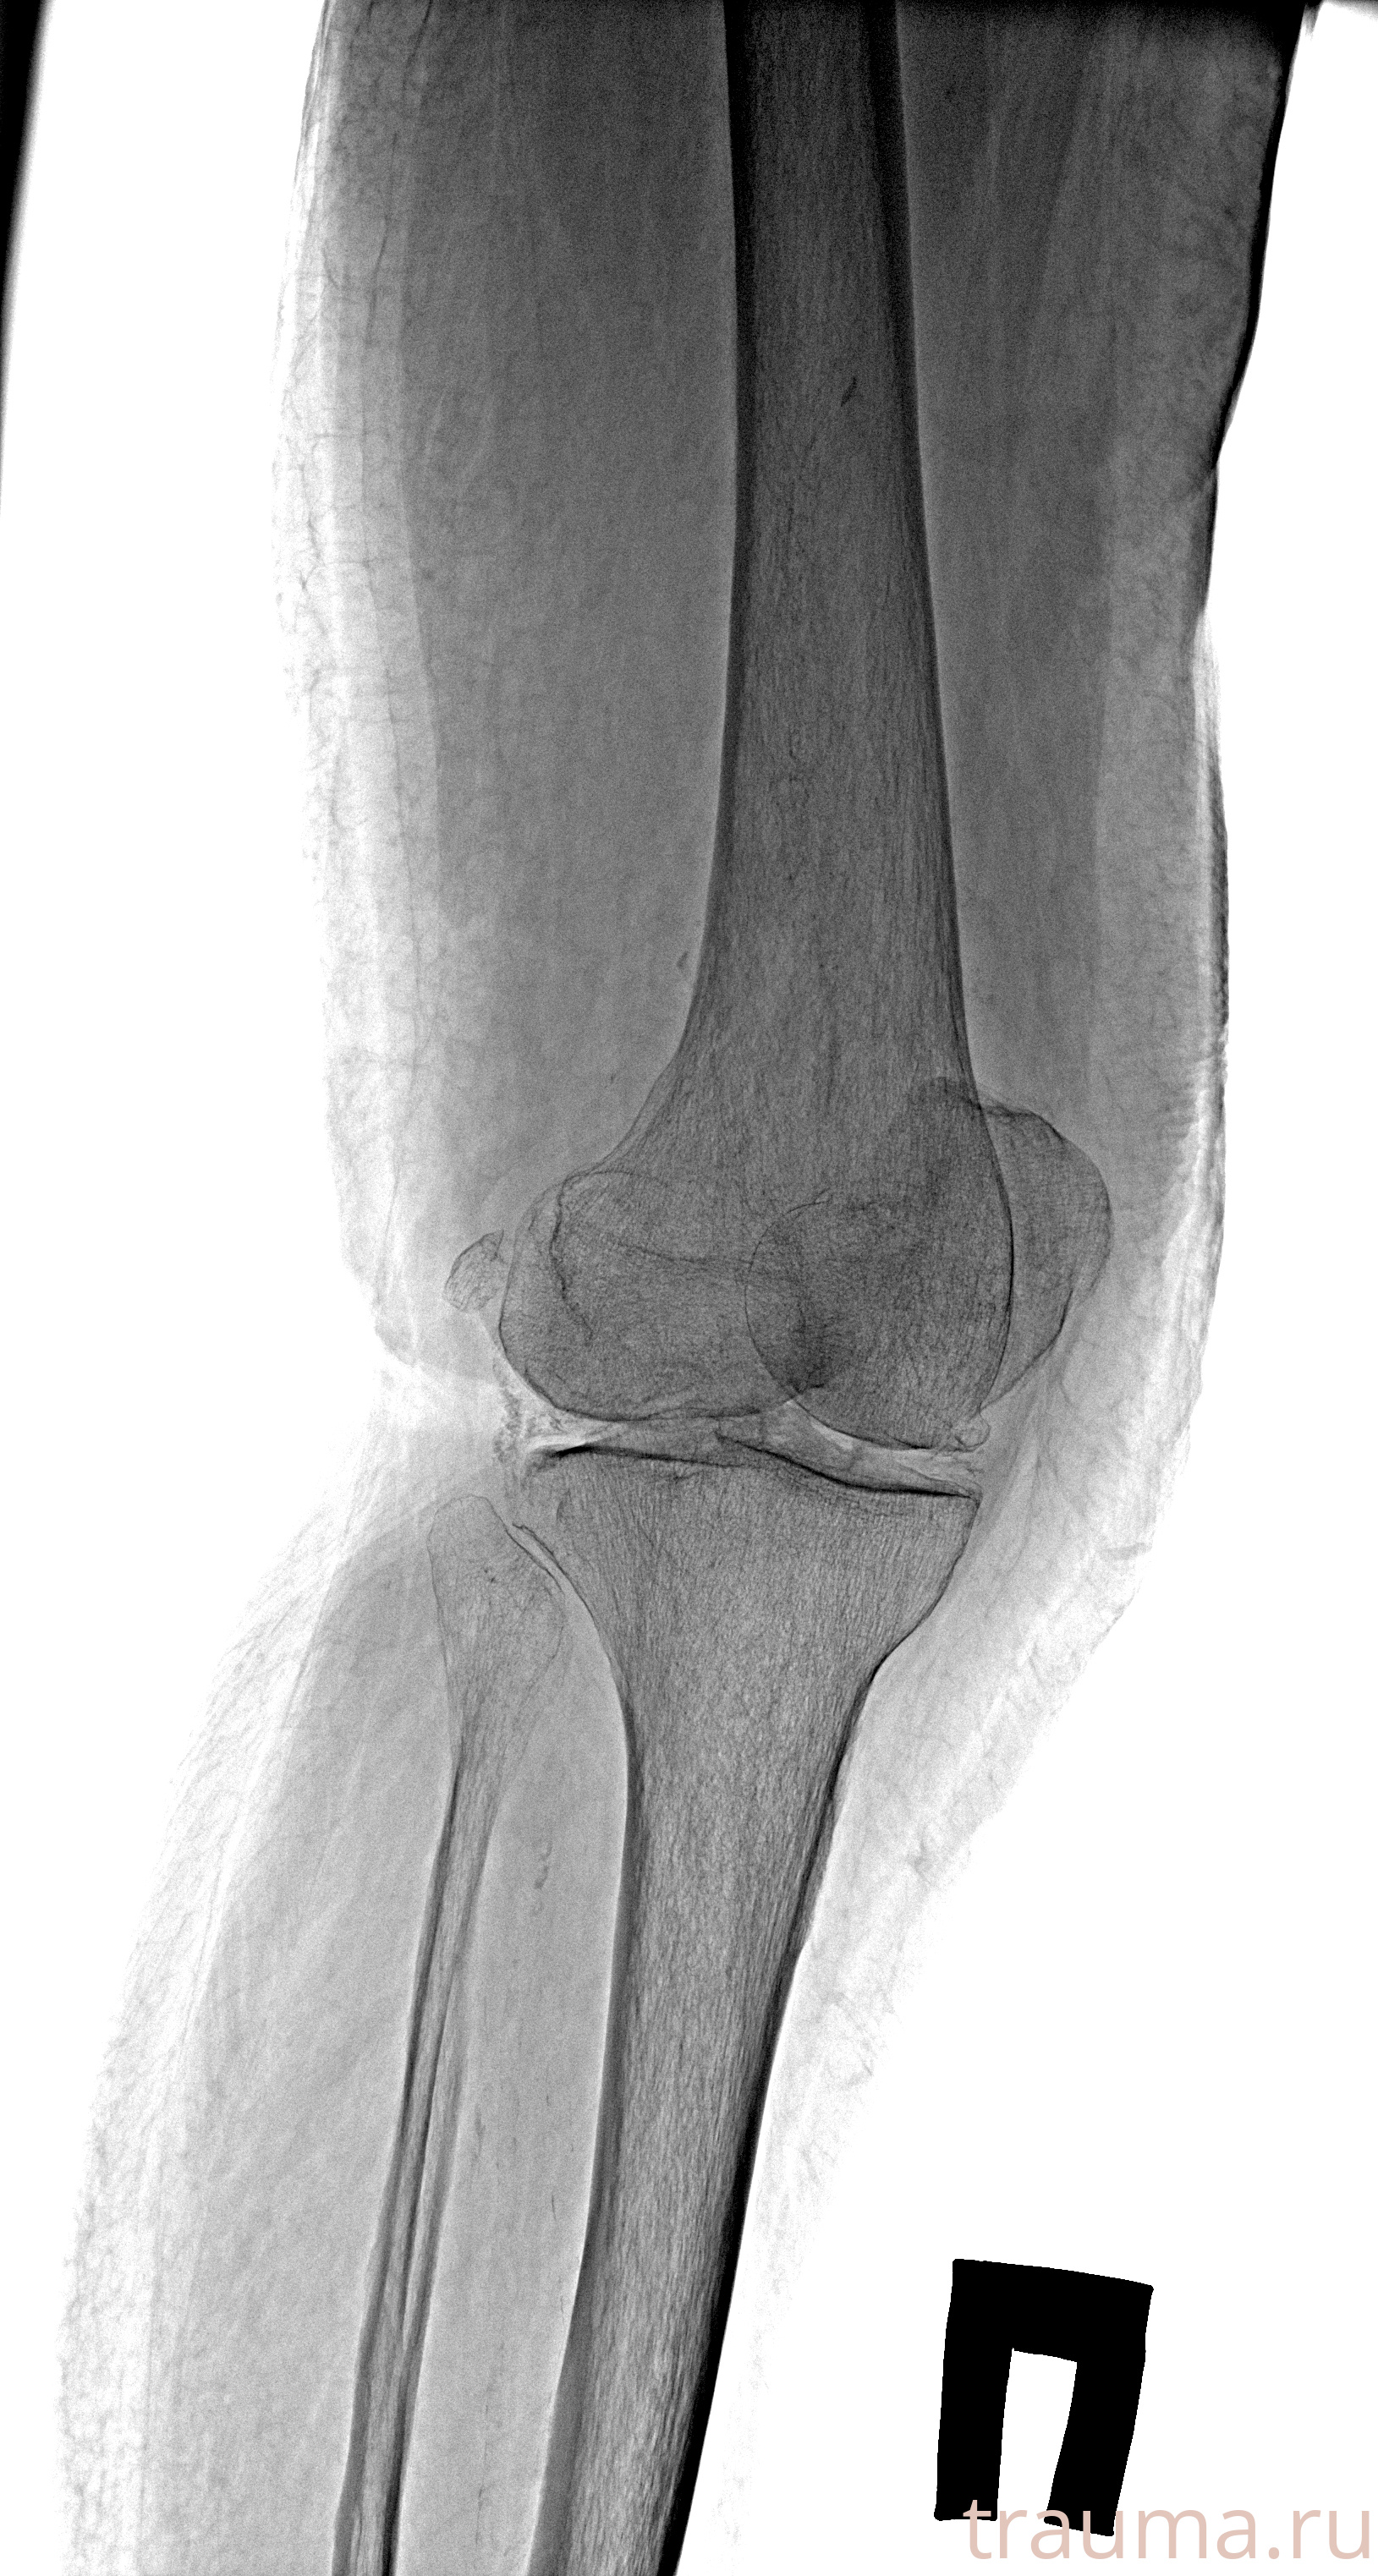

Рентгенограммы